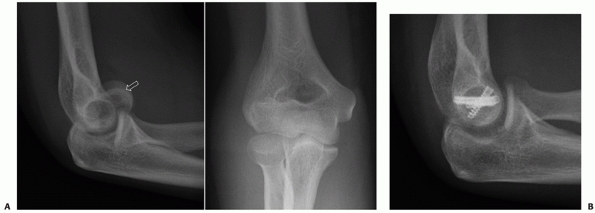

![]() |

FIGURE 33-17

Radiographs of an 88-year-old man with a transcolumn fracture (AO/OTA type A2) deemed medically unfit for surgery because of severe congestive heart failure and inoperable coronary artery disease (A,B). The patient was treated with a collar and cuff and early range of motion. Radiographs at 1-year follow-up (C,D). The patient has no pain with a functional range of motion (E,F). |